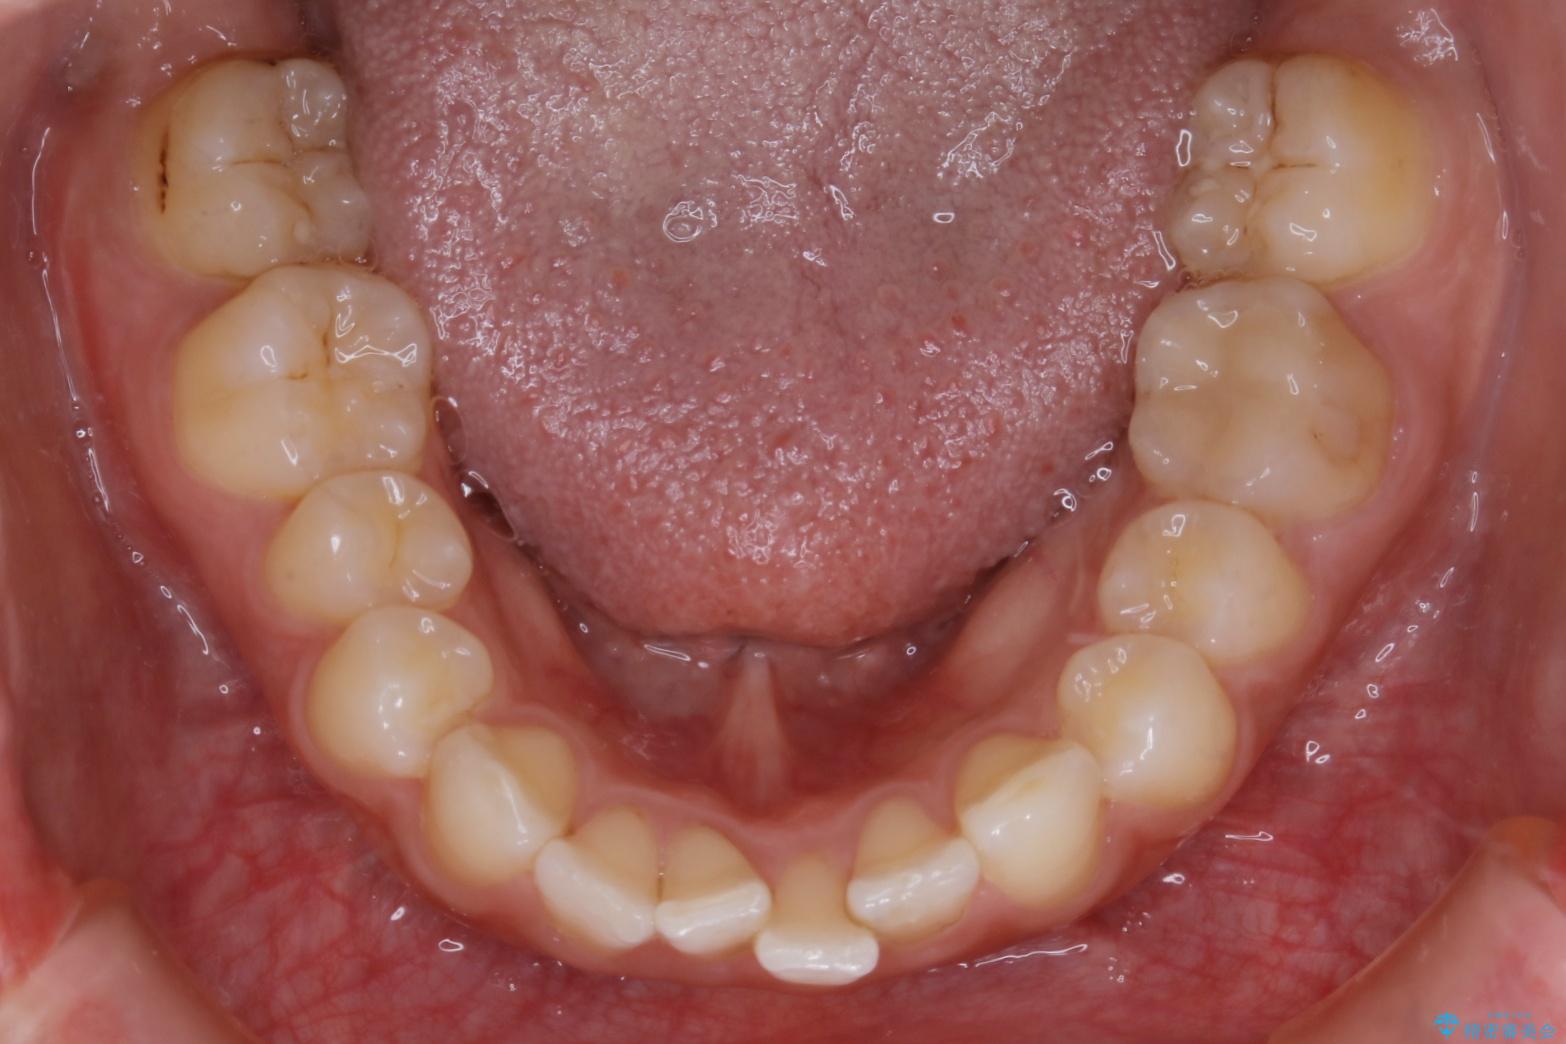

歯並びが悪くなる原因の一つに「歯列弓の狭窄」というものがあります。

奥歯や前歯が内側(舌側)に倒れ込んでしまったり、歯が生えてくる位置が内側になってしまうことにより歯並びのアーチが狭くなってしまうことを言います。

このような場合、歯並びのアーチを拡大してあげるだけでもガタつきを無くすためのスペースがかなり作れることがあります。